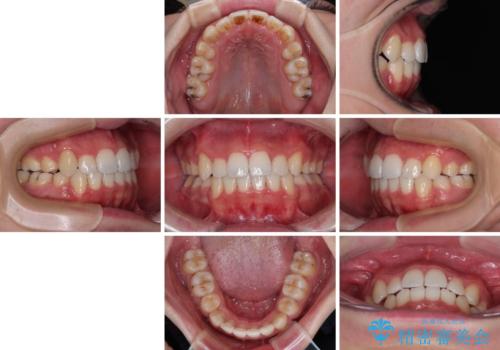

上下の八重歯とクロスバイト ワイヤー装置での抜歯矯正

前歯の歯列が整ったことで、歯磨きが大変やりやすくなり、患者様には大変満足していただけました。